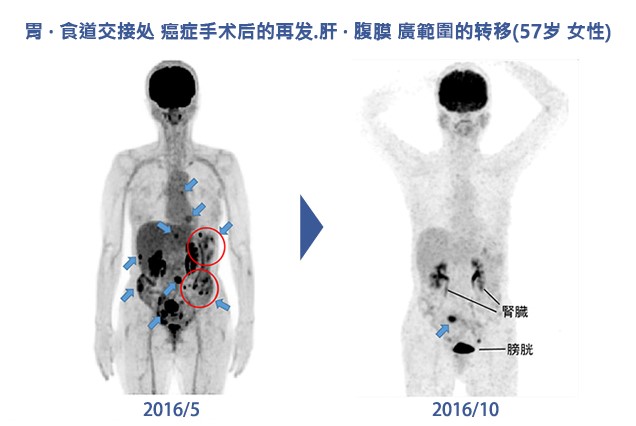

胃.食道结合部癌症手术后再发.肝.腹膜广范围转移(57岁女性)

癌症患者在.癌症再发.转移上没有办法全面控制.尤其是手术.放射线.抗癌治疗后.看不到的微小癌症引起的再发.转移.

为了让压制疾患的免疫系统.再次启动.需要做一些没有副作用.并压制癌症生长的免疫治疗.

我们体内免疫细胞中癌症的天敌是NK细胞和T细胞.目前针对NK细胞T细胞攻击破坏癌细胞研究.重点单纯的只是放在培养数量.活性化上面.

对于癌症患者来说.只是单纯的提升NK细胞和活性化来达到正常的数据.来治疗癌症.效果是有限的.最大的问题是癌症本身的多样性.以及回避性.

日本医疗团队院长提到.像这种癌症本身的多样性.以及回避性.最近美FDA公认的免疫抗癌剂PD-1抗癌剂(Opdivo+Yervoy)克攻破癌症.

免疫抗癌剂(Opdivo+Yervoy)的注射.让免疫细胞识别癌细胞.压制继续扩大的癌细胞,肿瘤,并且进行攻破,这时注射活性化的NK细胞和T细胞进行攻击破坏癌细胞.

博士曾经说过“如果没有让免疫细胞从新启动发挥作用的.免疫抗癌剂.只用以往的免疫细胞治疗癌症晚期患者.达不到像现在的50%~80%的效果”